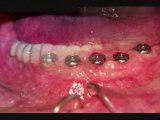

dentist eustis